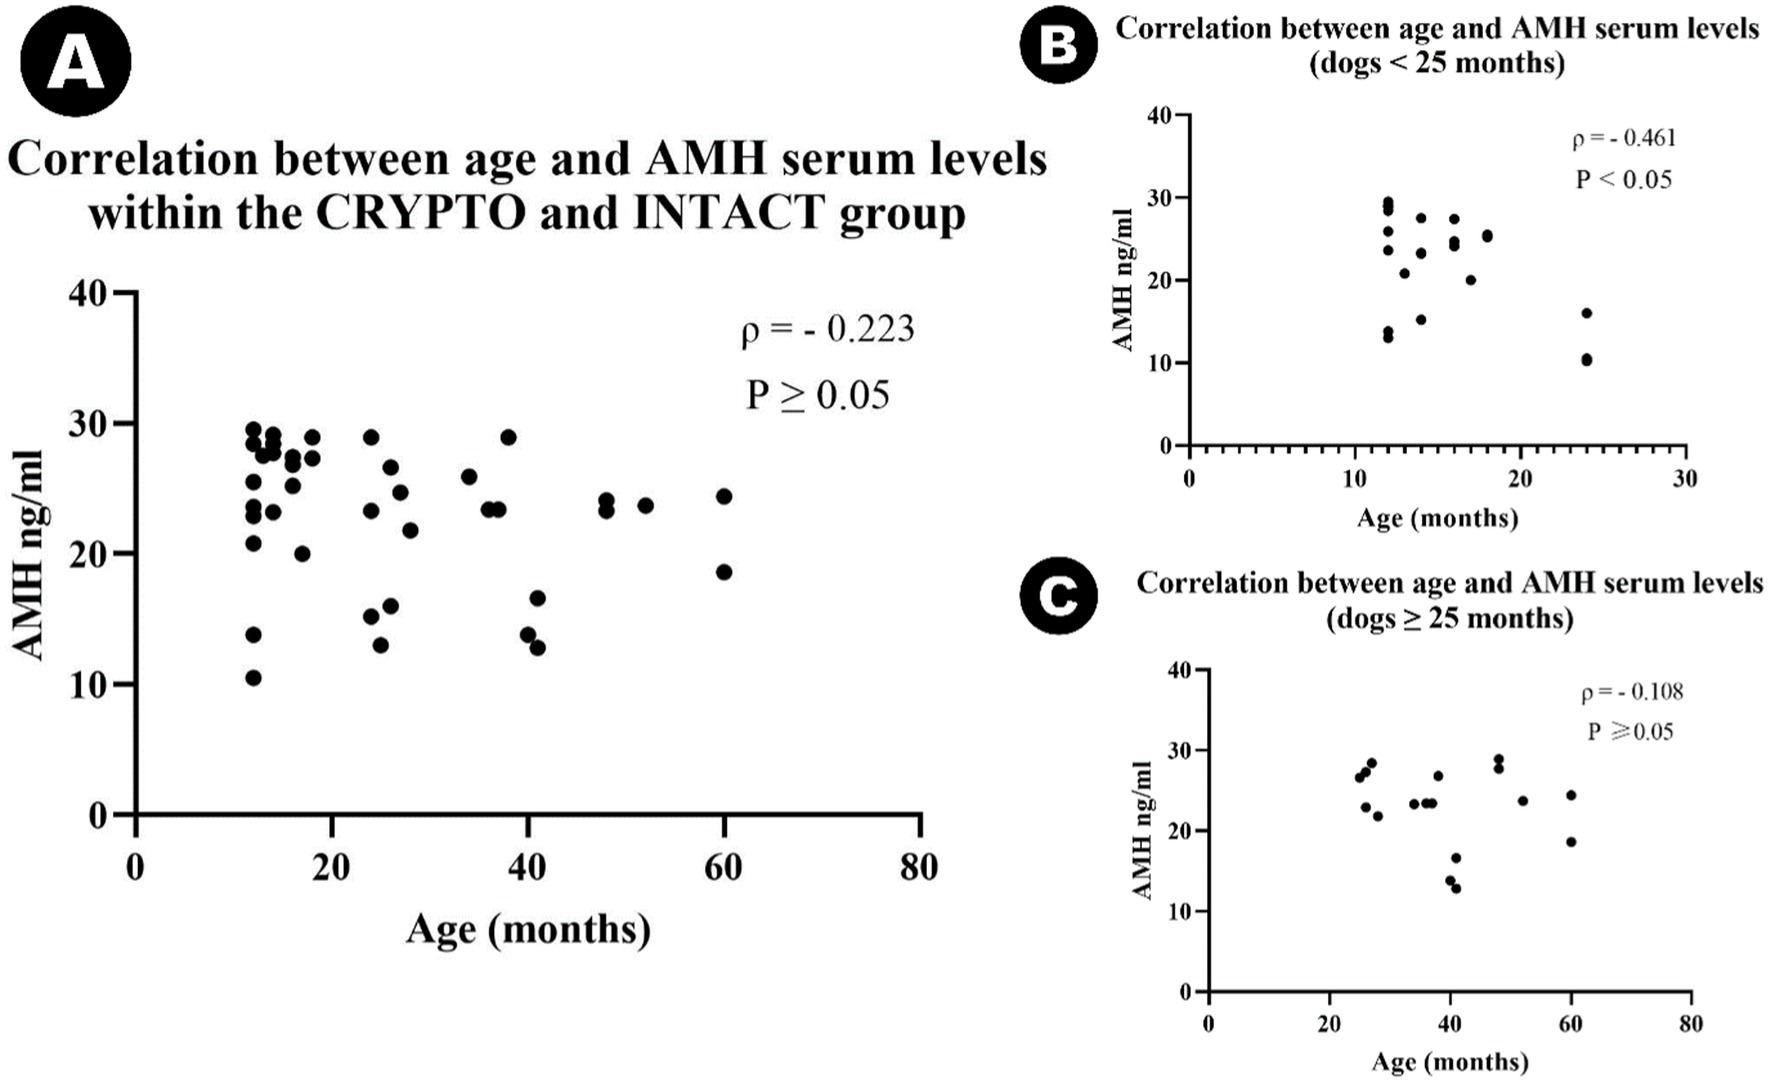

Se identificó un valor atípico en el grupo CRYPTO secundario a los cálculos de IQR. El valor de 10 ng/mL cayó por debajo del límite inferior (15,65 ng/mL) y, por lo tanto, se excluyó del análisis posterior. El resto de los datos sobre los niveles séricos de AMH mostraron diferencias significativas entre grupos específicos (Figura 2). El grupo CRYPTO tuvo niveles significativamente más altos de AMH (n = 19; mediana 27,4 ng/mL, IQR = 3,7) en comparación con los grupos INTACT (n = 20; mediana 20,4, IQR 9,25, p ≤ 0,01) y CASTRADOS (n = 10; 0,01 ± 0,01 ng/mL, p ≤ 0,001) (Figura 2A). Los sujetos del grupo CASTRATED (n = 20) mostraron solo valores séricos de AMH por debajo del límite de detección descrito del kit, lo que también provocó una diferencia significativa en comparación con los niveles séricos de AMH INTACT. Sin embargo, no se detectaron diferencias significativas entre las criptorquídeas unilaterales y bilaterales (p = 1.000) (Figura 2B), ni entre las criptorquídeas abdominales e inguinales (p = 1.000) (Figura 2C). Después de excluir el valor atípico en los valores de AMH, la mediana de edad en todos los grupos fue de 24 meses (n = 49, IQR = 27). No se observaron diferencias estadísticamente significativas en la distribución por edades entre los grupos CRYPTO, CASTRAED e INTACT p ≥ 0,05. En particular, se detectó una correlación negativa entre la edad y los niveles de AMH en todos los grupos (ρ = −0,415, p ≤ 0,01). Sin embargo, al calcular el análisis excluyendo a los individuos castrados, que suelen tener niveles bajos de AMH independientemente de la edad, la correlación entre la edad y los valores de AMH siguió siendo negativa (ρ = −0,223) pero ya no fue estadísticamente significativa (p ≥ 0,05) (Figura 3A). Además, cuando se investigó la relación entre la edad y los niveles séricos de AMH dentro de los grupos de edad separados, se identificó una correlación negativa entre las dos variables en perros menores de 24 meses (ρ = −0,461, p < 0,05) (Figura 3B). Por el contrario, esta correlación no fue significativa en la categoría de adultos (≥25 meses) (ρ = −0,108, p ≥ 0,05) (Figura 3C).